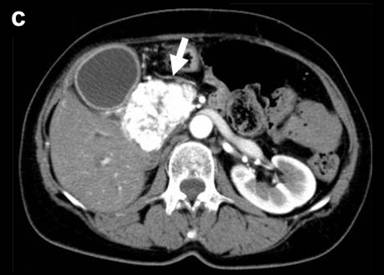

A 67-year-old female was referred to our hospital, complaining of jaundice, appetite loss and 3 kg of body weight loss over one month. She had undergone a thyroidectomy for a thyroid adenoma and a right oophorectomy for an ovarian tumor at 41 years of age and a right nephrectomy for renal cell carcinoma at 47 years of age. Laboratory data demonstrated mild liver dysfunction due to obstructive jaundice without elevation of plasma CEA and CA 19-9 levels. Computed tomography (CT) demonstrated a remarkably enhanced tumor measuring 55x40 mm in diameter in the head, two tumors measuring 2.0 and 1.8 cm in the body, and two tumors measuring 1.2 and 1.0 cm in the tail with a similar enhancing effect (Figure 1abc). CT angiography did not demonstrate any abnormalities of the arteries and the dorsal pancreatic artery branching from the origin of the splenic artery (Figure 1d). Magnetic resonance imaging demonstrated obstruction on the intrapancreatic bile duct due to a pancreatic head tumor and a slight dilatation of the main pancreatic duct in the body and tail of the pancreas. Fluorine-18 fluorodeoxyglucose positron emission tomography detected an elevated uptake in the isolated multifocal metastatic pancreatic tumors without any extrapancreatic uptake. A biliary drainage tube was inserted endoscopically. Cytology of the pancreatic juice was negative. The patient was diagnosed with isolated pancreatic metastases from renal cell carcinoma. The huge tumor located in the head was resected by a pancreaticoduodenectomy and the four tumors located in the body and in the tail of the pancreas were resected by a distal pancreatectomy, preserving the cervical portion. Intraoperative confirmation of arterial perfusion in the middle segment was necessary. In other cases, a total pancreatectomy should be done. Enucleation was not considered due to the risk of main pancreatic duct injury.

Figure 1. Preoperative computed tomography. Pancreatic metastatic tumors were detected as being demarcated enhanced tumors in the tail (a.) and body (b.) of the pancreas. A very large tumor occupied the entire head of the pancreas (c.). The common bile duct was compressed by the tumor located in the head of the pancreas (d.). |